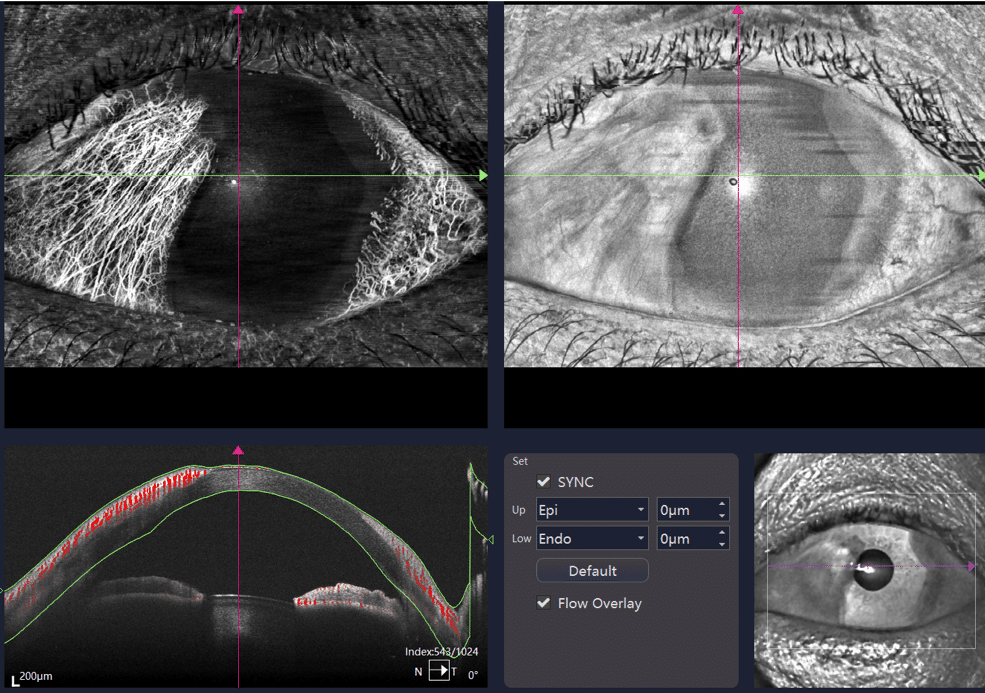

- Wide-field OCTA

- Choroid OCTA with Quantification Parameters

- HD Anterior Scan with Anterior OCTA